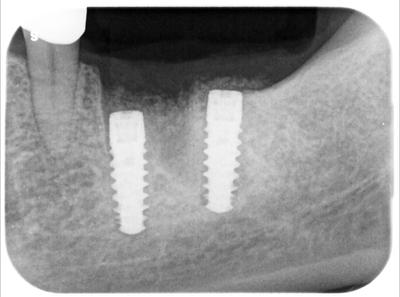

┏6歯根破折し抜歯、┏67欠損のため、同部に対しインプラント処置。

使用インプラントはITI(スイス)。